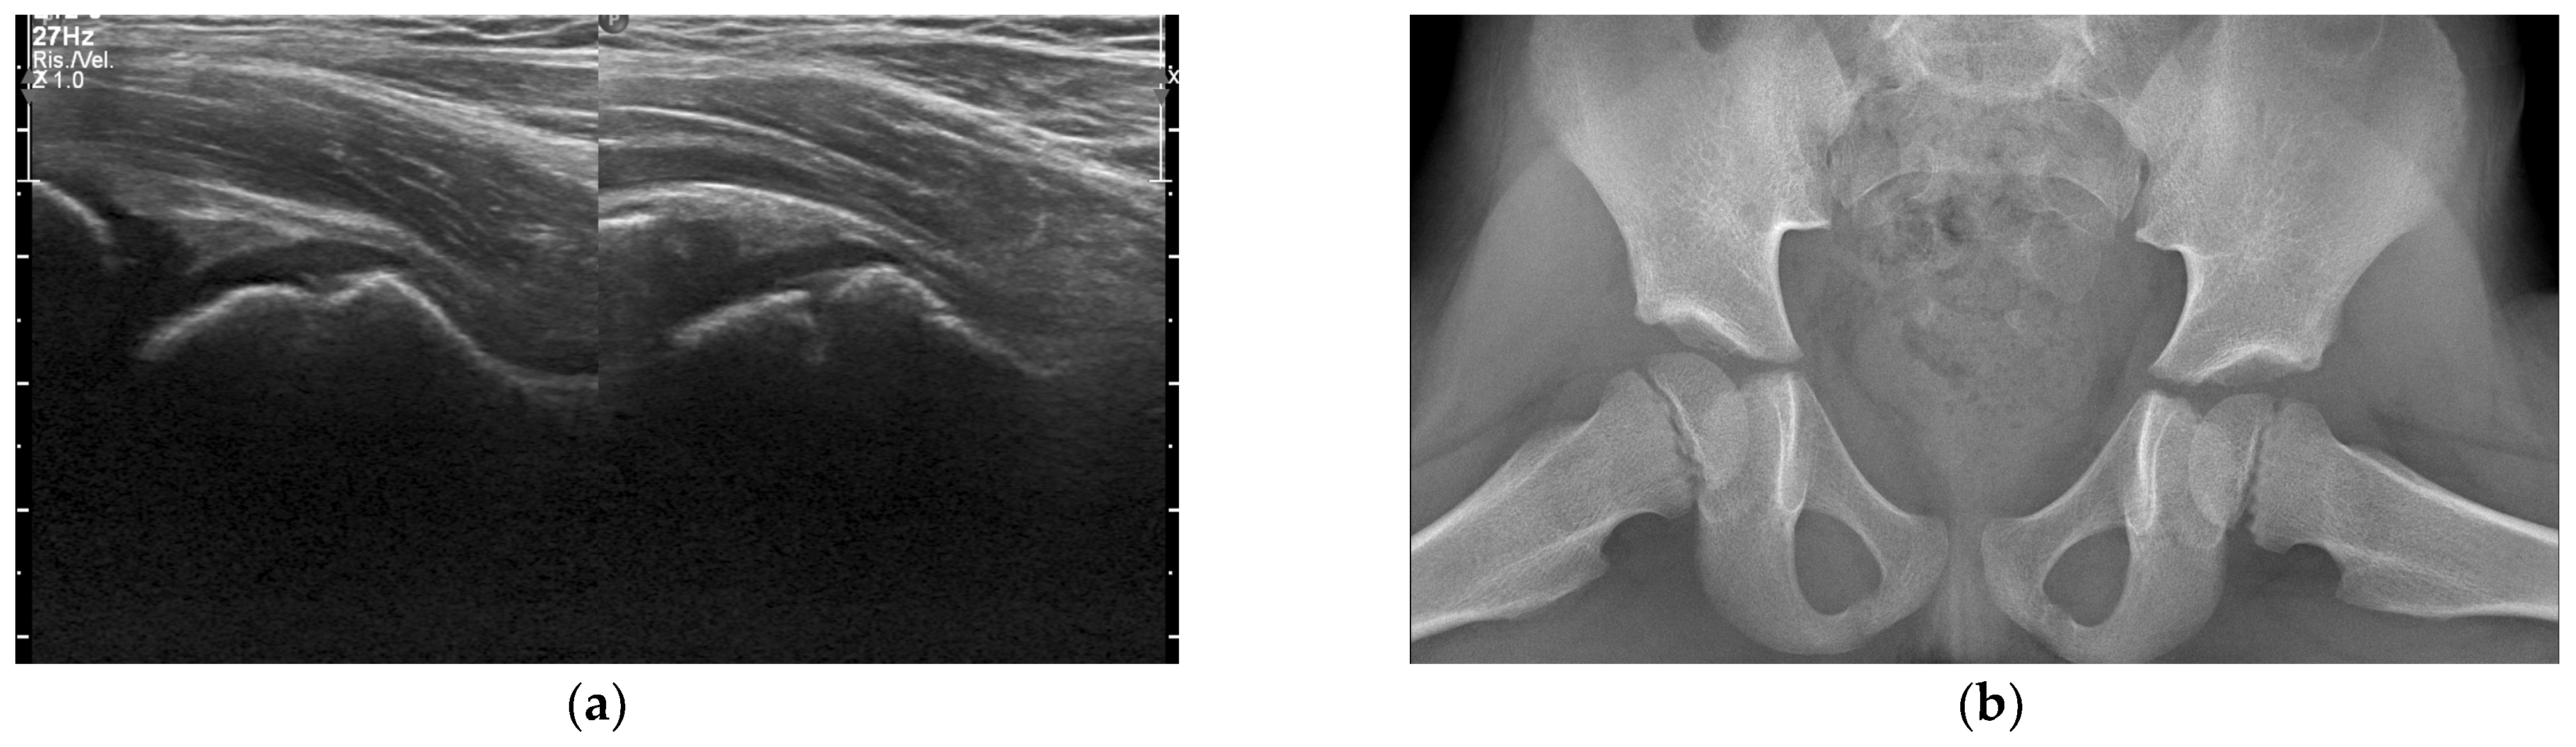

- Trusen, A.; Beissert, M.; Schultz, G.; Chittka, B.; Darge, K. Ultrasound and MRI features of pyomyositis in children. Eur. Radiol. 2003, 13, 1050–1055. [Google Scholar] [CrossRef]